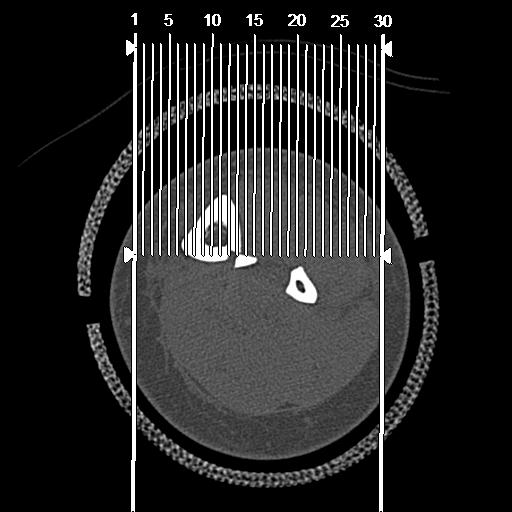

56476 8/28 4R 1/21 2R 左足関節 デジカメ写真 72歳女性 右足関節AS

102755 1/4 2R 1/15 2R 右足関節 68歳女性 右三果脱臼骨折